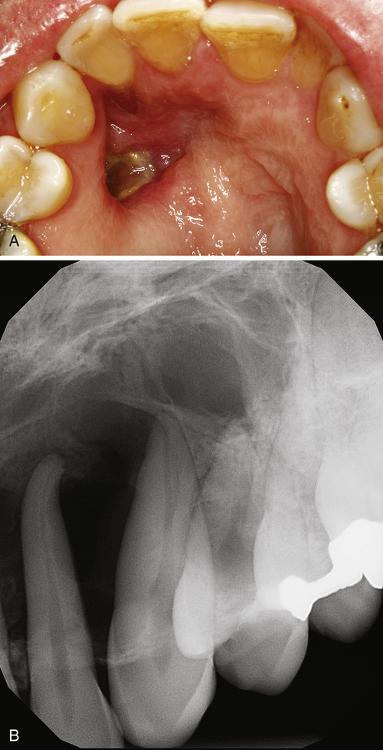

Radiolucent lesion with irregular, ragged margins surrounding the crown of an impacted third molar in a 56-year-old woman. This was clinically considered to be a dentigerous cyst.

odontogenic carcinoma

Nineteen years previously, a large odontogenic keratocyst (OKC) with areas of epithelial dysplasia had been removed from the ascending ramus.